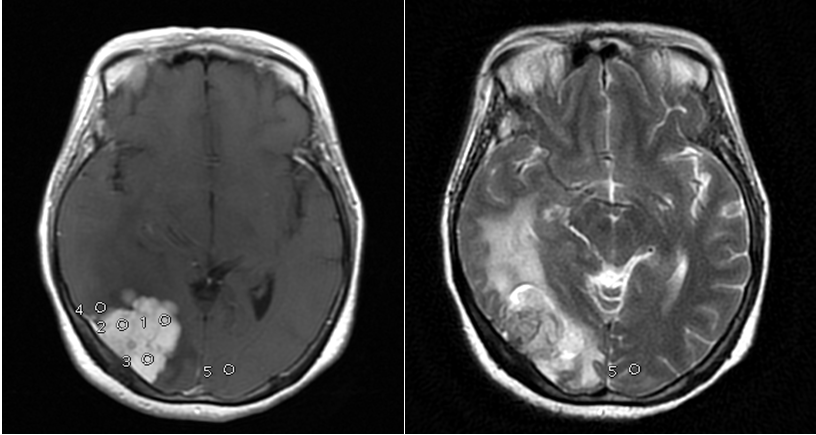

In our study showed that tumor volume as suggested by Hale et al. as the strongest predictor of atypical meningioma, didn’t always correlate with meningioma grade. In our samples there were 6 (37.5%) meningioma WHO grade I with tumor volume more than 50 cm3, with the biggest volume 252.4cm3 (Figure 1) and 1(33%) of atypical meningioma (WHO grade II) with tumor size 28.5 cm3. Hale also suggested that peritumoral edema as predictor of higher grade meningioma. In our study we found 1 case of anaplastic meningioma (WHO grade III) with mild edema and conversely, 44% of meningioma WHO grade I with severe edema (Figure 2). In that study also found that tumor along the falx and convexity were more often atypical than in skull base or posterior fossa. In this study, samples of meningioma WHO grade I mostly (37.5%) located in convexity, 25% in falx and in atypical meningioma WHO grade II turned out 67% located in skull base (Figure 3). That study also found that tumor necrosis was associated with an increased risk for atypical meningioma. In this study, we found 67% of atypical meningioma WHO grade II without tumor necrosis and 44% of typical meningioma WHO grade I with tumor necrosis (Figure 4). 1 case of anaplastic meningioma (WHO grade III) in our study had large tumor volume (>50 cm3), located in convexity and with tumor necrosis although there was one predictor that didn’t suit which in this case had mild peritumoral edema (Figure 5).

Figure 4 Left image: Female 46 y.o with meningioma, transitional type, WHO Grade I with tumor necrosis; Right image: Male 67 y.o with atypical meningioma, WHO grade II, without tumor necrosis.